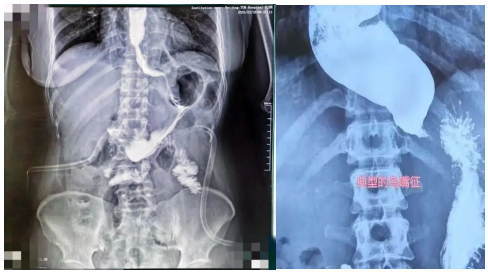

作为国内外科的知名专家,路夷平教授擅长胃肠道疾病的微创手术治疗,尤其在胃肠肝胆胰肿瘤、巨大食管裂孔疝、贲门失迟缓症的治疗上有着深厚的造诣。接诊常女士后,路夷平教授仔细翻阅她的病历,并安排一系列详细检查,最终常女士被确诊为“贲门失迟缓症”。这是一种由于食管下端括约肌功能障碍导致的疾病,患者会出现吞咽困难、食物反流、呕吐等症状,严重时甚至会影响生活质量。通过造影检查显示,常女士食管扩张的几乎和正常人的胃一样大小。